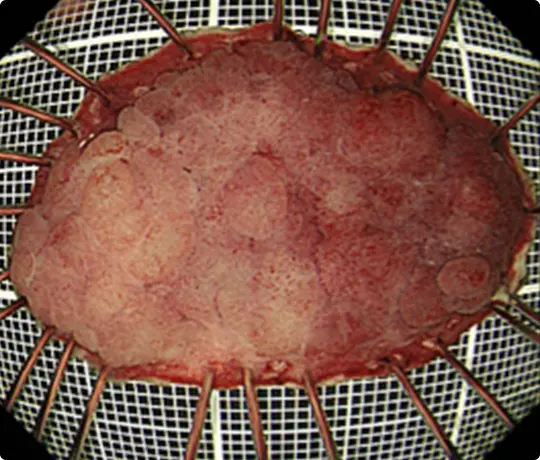

切除した検体をピンで伸ばして、ホルマリンで固定後、病理診断を行います。中央に見える赤く隆起している部分が腫瘍です(青い色素をかけています)。

体外に摘出した咽頭癌をピンで張り付けて伸ばしています。

左(通常観察):白い点は、病変のすぐ外側に電気メスで付けたマークです。全周性にマークが認められ、切除予定だった範囲を切除できたことが分かります。

右(ヨード染色後):薬液(ヨード)で染色すると、黄色矢印内に色の違う部分が出てきます。この部分が咽頭癌です。病理検査(顕微鏡での分析)で咽頭癌は完全に切除されており、治癒と判定されました。

切除した検体です。

切除した検体を展開し、ピンで伸ばしてヨード染色をしています。黄色いところが食道がんの部分です。ホルマリンで固定後、病理診断を行います。病理診断で腫瘍は完全に切除されており、治癒と判定されました。

切除した検体をピンで伸ばしています。ホルマリンで固定後、病理診断を行います。病理診断で腫瘍は完全に切除されており、治癒と判定されました。

切除した検体をピンで伸ばしています。ホルマリンで固定後、病理診断を行います。病理診断で腫瘍は完全に切除されており、治癒と判定されました。